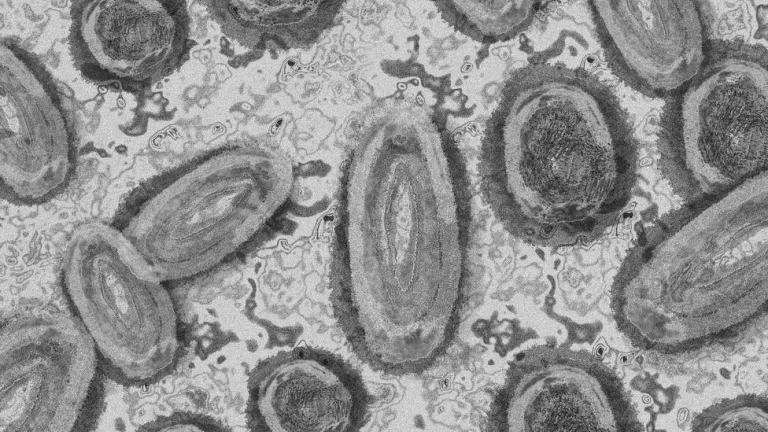

La viruela del mono se extiende por Euskadi con 85 nuevos casos

Euskadi ha identificado en total 85 casos de infección por viruela del mono, conocida también como "monkeypox", lo que supone 66 más que en la última actualización hecha pública por el Departamento de Salud el pasado 29 de junio.

La viruela del mono es una enfermedad muy poco frecuente, que generalmente se presenta con fiebre, mialgias, adenopatías (inflamación en los ganglios), y erupción en manos y cara, similar a la varicela.